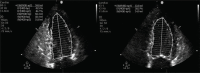

Herein, we report the case of a 56-year-old male patient with acute myeloid leukemia (AML) in remission who had asymptomatic myocardial ischemia on myocardial perfusion imaging and transthoracic echocardiography. Angiography did not reveal any significant coronary artery disease. Although the etiology is not entirely clear, this case suggested that myocardial perfusion imaging should be considered in patients with AML who received idarubicin to screen for possible myocardial dysfunction.